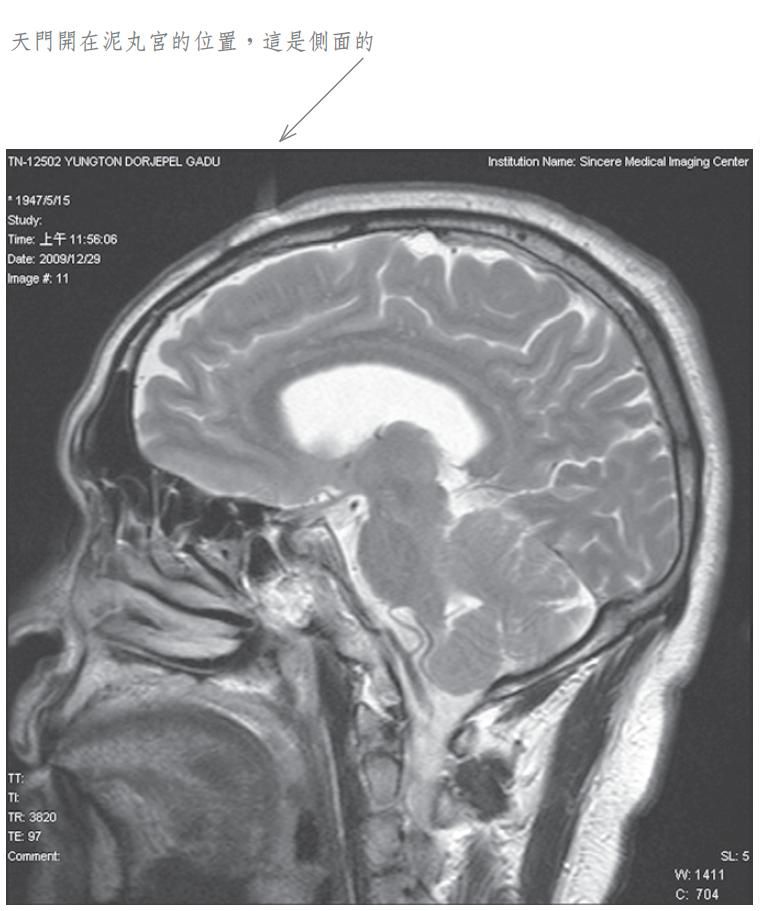

當我將此種修法中發生之覺受稟報佛陀師父時,佛陀師父又為我傳了秘密口訣。經過一段時日,佛陀師父在公開開示的法音帶中,才提到我曾經修法達到化身境的初級,即是素化身的意思。為了讓眾生明瞭佛法的偉大,事隔多年之後,我特別於二零零九年十二月廿九日,到中心綜合醫院安排磁振造影(MRI)頭部的攝影檢查,結果發現泥丸宮的部位出現一個1.5公分寬深的開口,同時拍下了有一股神識出氣衝出頭部的實況。負責檢查的醫生非常驚訝稱奇,但無法解釋其原因,因而將它歸因於非人之所為。我其實非常清楚,我的神識化身本來就是從這裡出入的,以下是在醫院MRI檢查的掃瞄片。